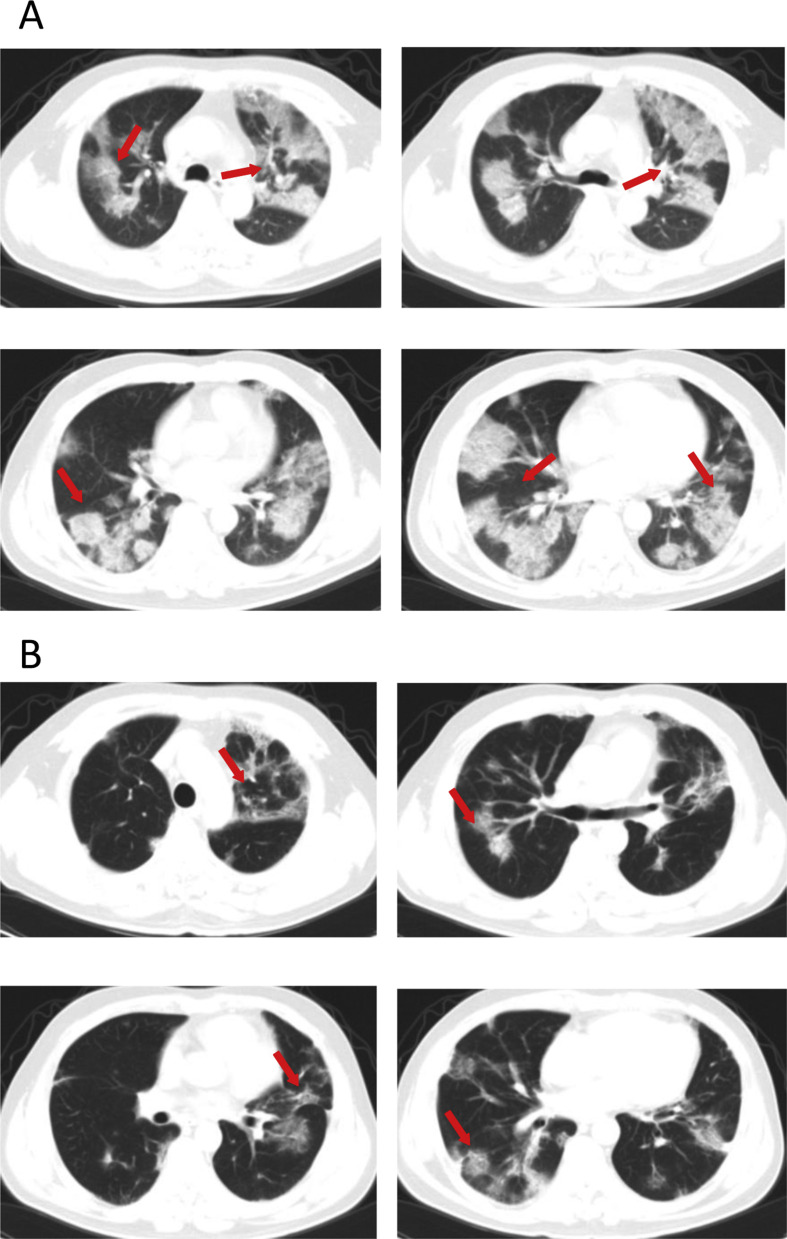

Admission examination showed a temperature of 36.6 °C, a pulse of 88/min, a respiratory rate of 20/min, and a blood pressure of 138/85 mmHg (Table 1). No obvious abnormality was found on physical examination. Blood test revealed elevations in WBCs (10.11 × 109/L) and neutrophils (9.19 × 109/L) and reductions in lymphocytes (0.6 × 109/L) (Table 2 ). Laboratory studies showed increases in FPG (20.76 mmol/L) pro-BNP (170 pg/mL; normal references: 0–125 pg/mL), fibrinogen C (5.22; normal references: 2.03–4.72 g/L), fibrin degradation product (FDP, 2.06 mg/L; normal references: 0.00–2.01 mg/L), total bilirubin (20.5, mmol/L; normal references: 3.4–17.1 mmol/L) and lactate dehydrogenase (LDH, 374 U/L; normal references: 105–245 U/L) and decreased IgG levels (8.0 g/L; normal references: 11.5–14.2 g/L). His PO2 was reduced (76.6 mmHg) and PCO2 was elevated (47.8 mmHg), and the oxygen saturation was unnormal (94.6%). Chest CT scan on February 6, 2020 showed diffuse multiple patchy exudates with partial interlobar septation, suggesting viral pneumonia (Fig. 2 A). Apart from nutritional support and oxygen supplementation (5 mL/min), the patient was given recombinant interferon α aerosol (500 × 106 U twice daily), lopinavir-ritonavir, metformin (0.5 g twice daily), intravenous ceftazidime (2 g twice daily), and oral glimepiride (2 mg once daily). The patient's condition worsened despite treatment. On February 8, the patient received mechanical ventilation. Blood coagulation test on February 9 showed marked elevations in fibrinogen C (6.75 g/L), FDP (20.55 mg/L) and D-dimer (2744 ng/mL; normal references: 0–231 ng/mL) and subcutaneous low molecular weight heparin was started on February 10. Intravenous insulin (20IU/daily) and intravenous moxifloxacin (0.4 g once daily) were given on February 16. The patient gradually improved. CT scan on February 23, 2020 showed multiple bilateral patchy shadows, partial exudates and fibrotic changes, which markedly improved versus changes at admission (Fig. 2B) and laboratory studies on February 23, 2020 revealed normal WBC count, lymphocyte and neutrophil count and coagulation parameters were also normal. The patient was discharged from the hospital on March 8, 2020.

Figure 2.

(A) Chest CT scan of a 48-year old male patient with fever and cough for 9 days who had confirmed COVID-19 pneumonia on February 6 diffuse multiple patchy exudates with partial interlobar septation, suggesting viral pneumonia. (B) CT scan on February 23, 2020 reveals multiple bilateral patchy shadows, partial exudation and fibrotic changes, which are markedly improved versus changes at admission.